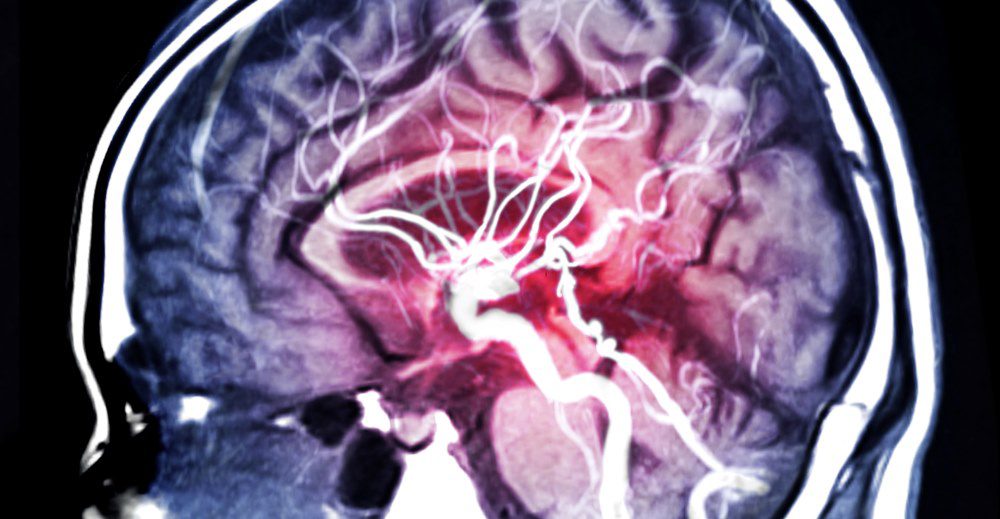

Exploring Aneurysm Risk Factors in Different Age Groups

Aneurysms, characterized by a strange bulge in a blood vessel’s wall, can create major health risks for people of all kinds. Being aware of which demographics are more likely to experience aneurysms, as well as age-specific risk factors and guidelines to follow, is crucial for preventing and managing this potentially life-threatening disease.This article will detail … Read more